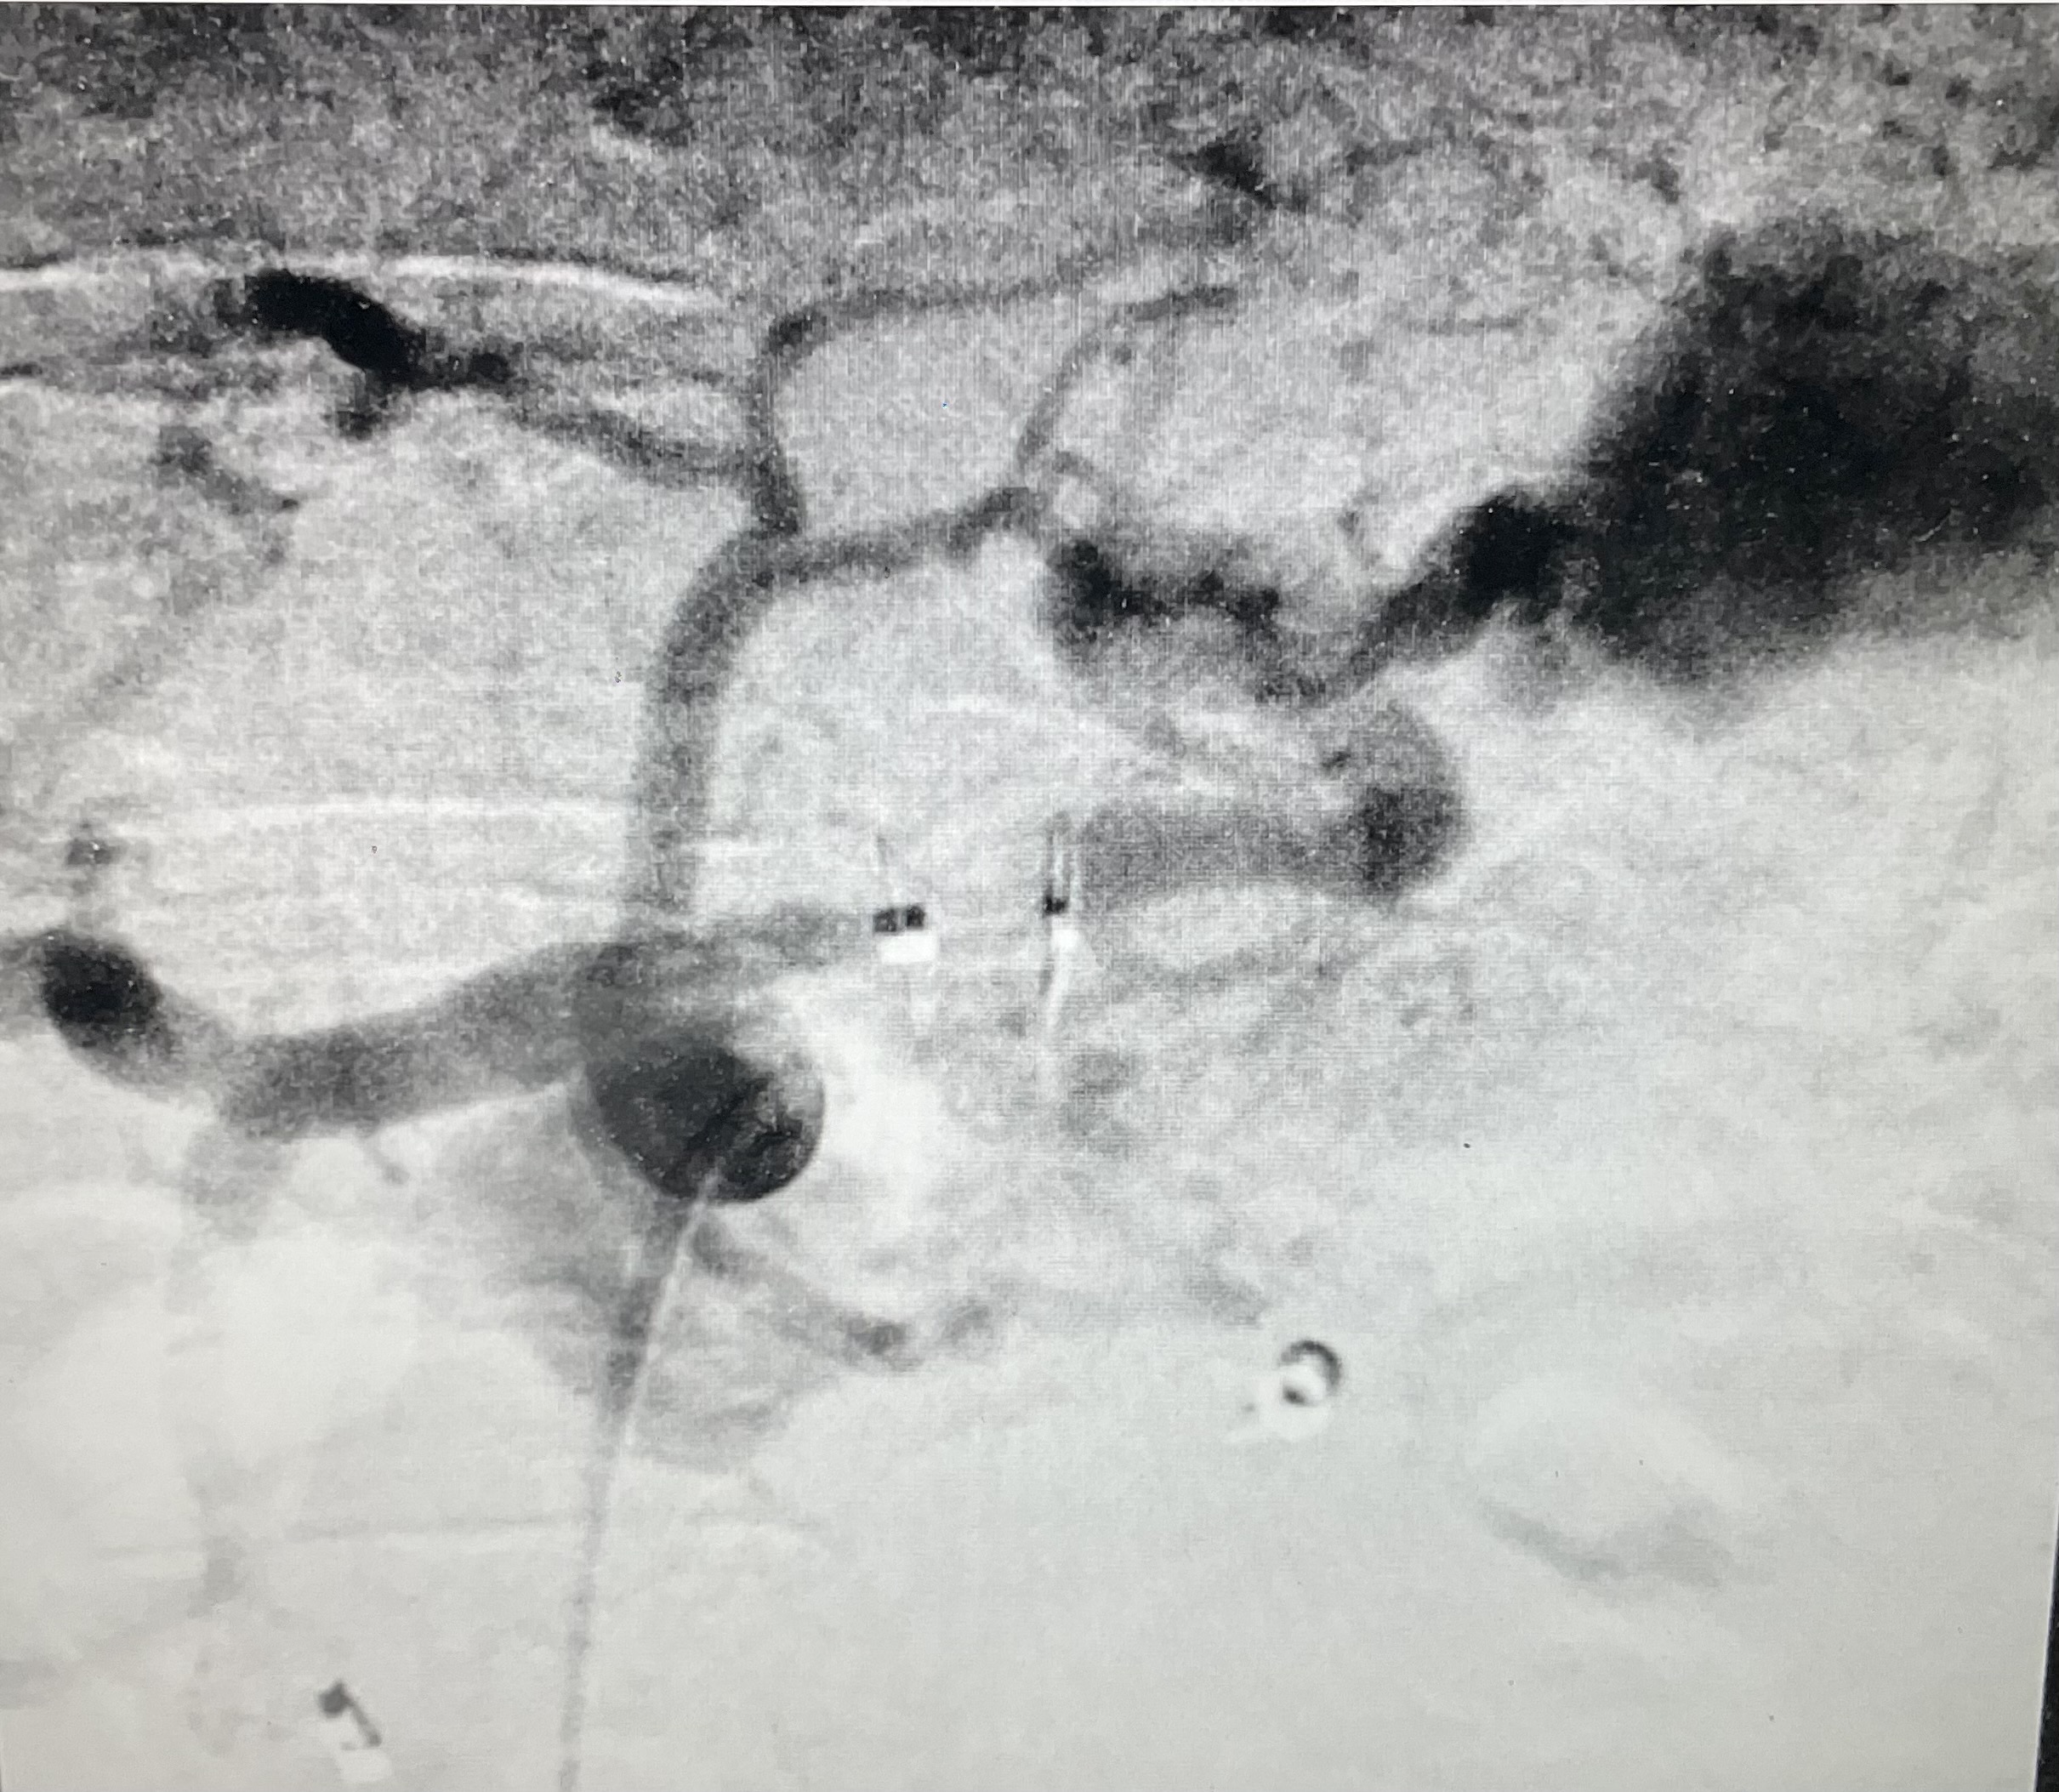

3. Заполнение дистальной части селезеночной артерии через множественные коллатерали при контрастировании а. gastroduodenalis | |

4. Стентирование нижней полой вены и правой печеночной вены. | |